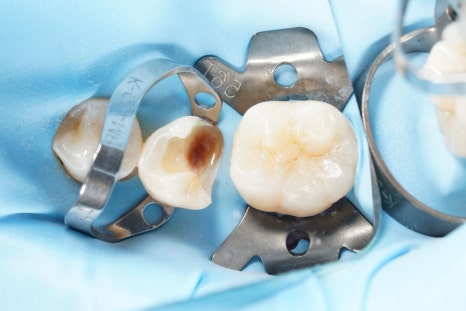

그리고 이렇게 하기 위해서는

러버댐이라는 재료를 잘 써야 해요.

러버댐을 잘 쓰는 것이

가장 중요한 첫단계입니다.

러버댐이라는 재료는

그냥 썼다고해서 다 된 게 아니라

그 목적을 이루기 위해 필요한 여러 원칙들을

하나하나 지켜야만

원하는 결과를 얻을 수 있겠죠.

어금니, 앞니 가릴 것 없이

중요한 접착의 순간에

이렇게 러버댐을 사용하는 것,

그래서 구강 내에 있는

뺨과 혀,

피와 침과 습기로부터

치아를 완전히 격리하고 방습하는 것.

그것이 교과서에 적힌 원칙이고

결과를 High-end로 유지할 수 있는

비결입니다.